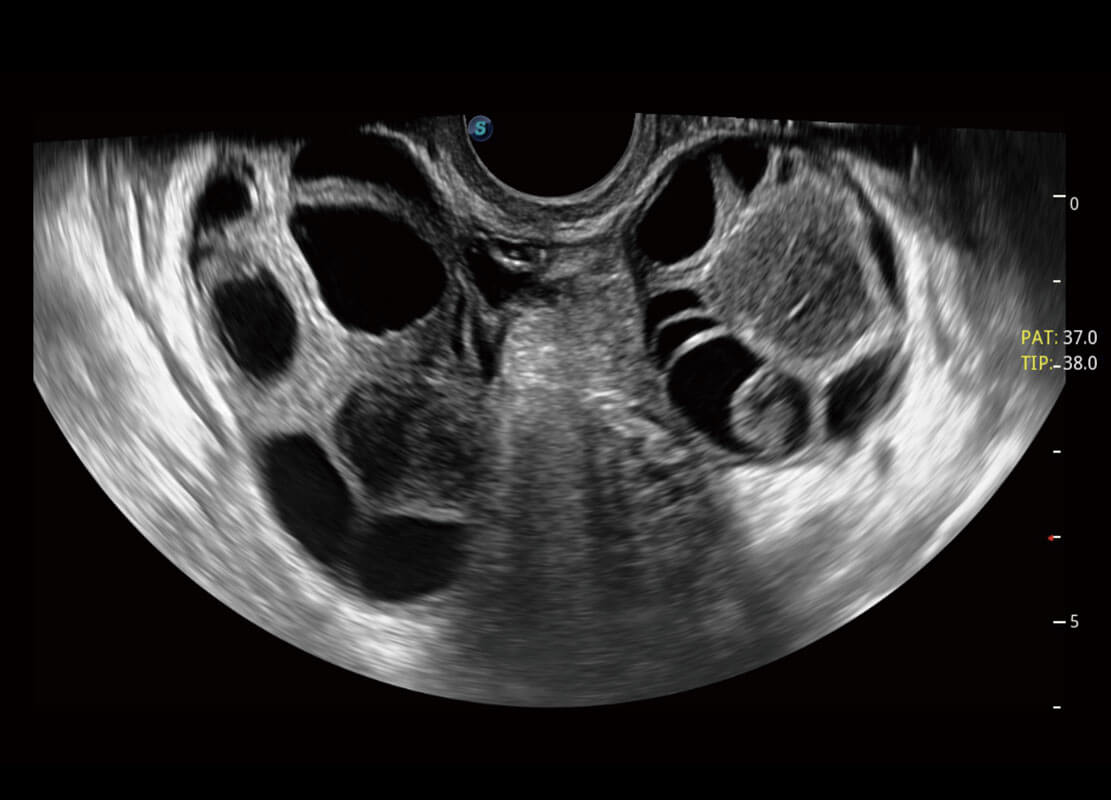

盆底超声

P60为盆底超声检查提供应用方案,多种腔内及腹部容积探头提供从二维、三维到四维的优异图像品质,实时快速三维容积数据获取,专业的测量工具包等人性化设计,为超声医生诊断提供有力保障。

Lev.Hiat A-r: 16.33 cm2

Lev.Hiat H-r: 53.70 mm

Lev.Hiat W-r: 43.96 mm

Lt-LUG-r: 24.16 mm

Rt-LUG-r: 19.94 mm

S-Pelvic

能够简化盆底检查的操作流程,可在二维模式及三维成像模式下实现一键自动提取出标准切面、自动识别当前切面、自动测量,提升盆底检查的高效性,同时也能让青年医生快捷的获得准确的检查结果。